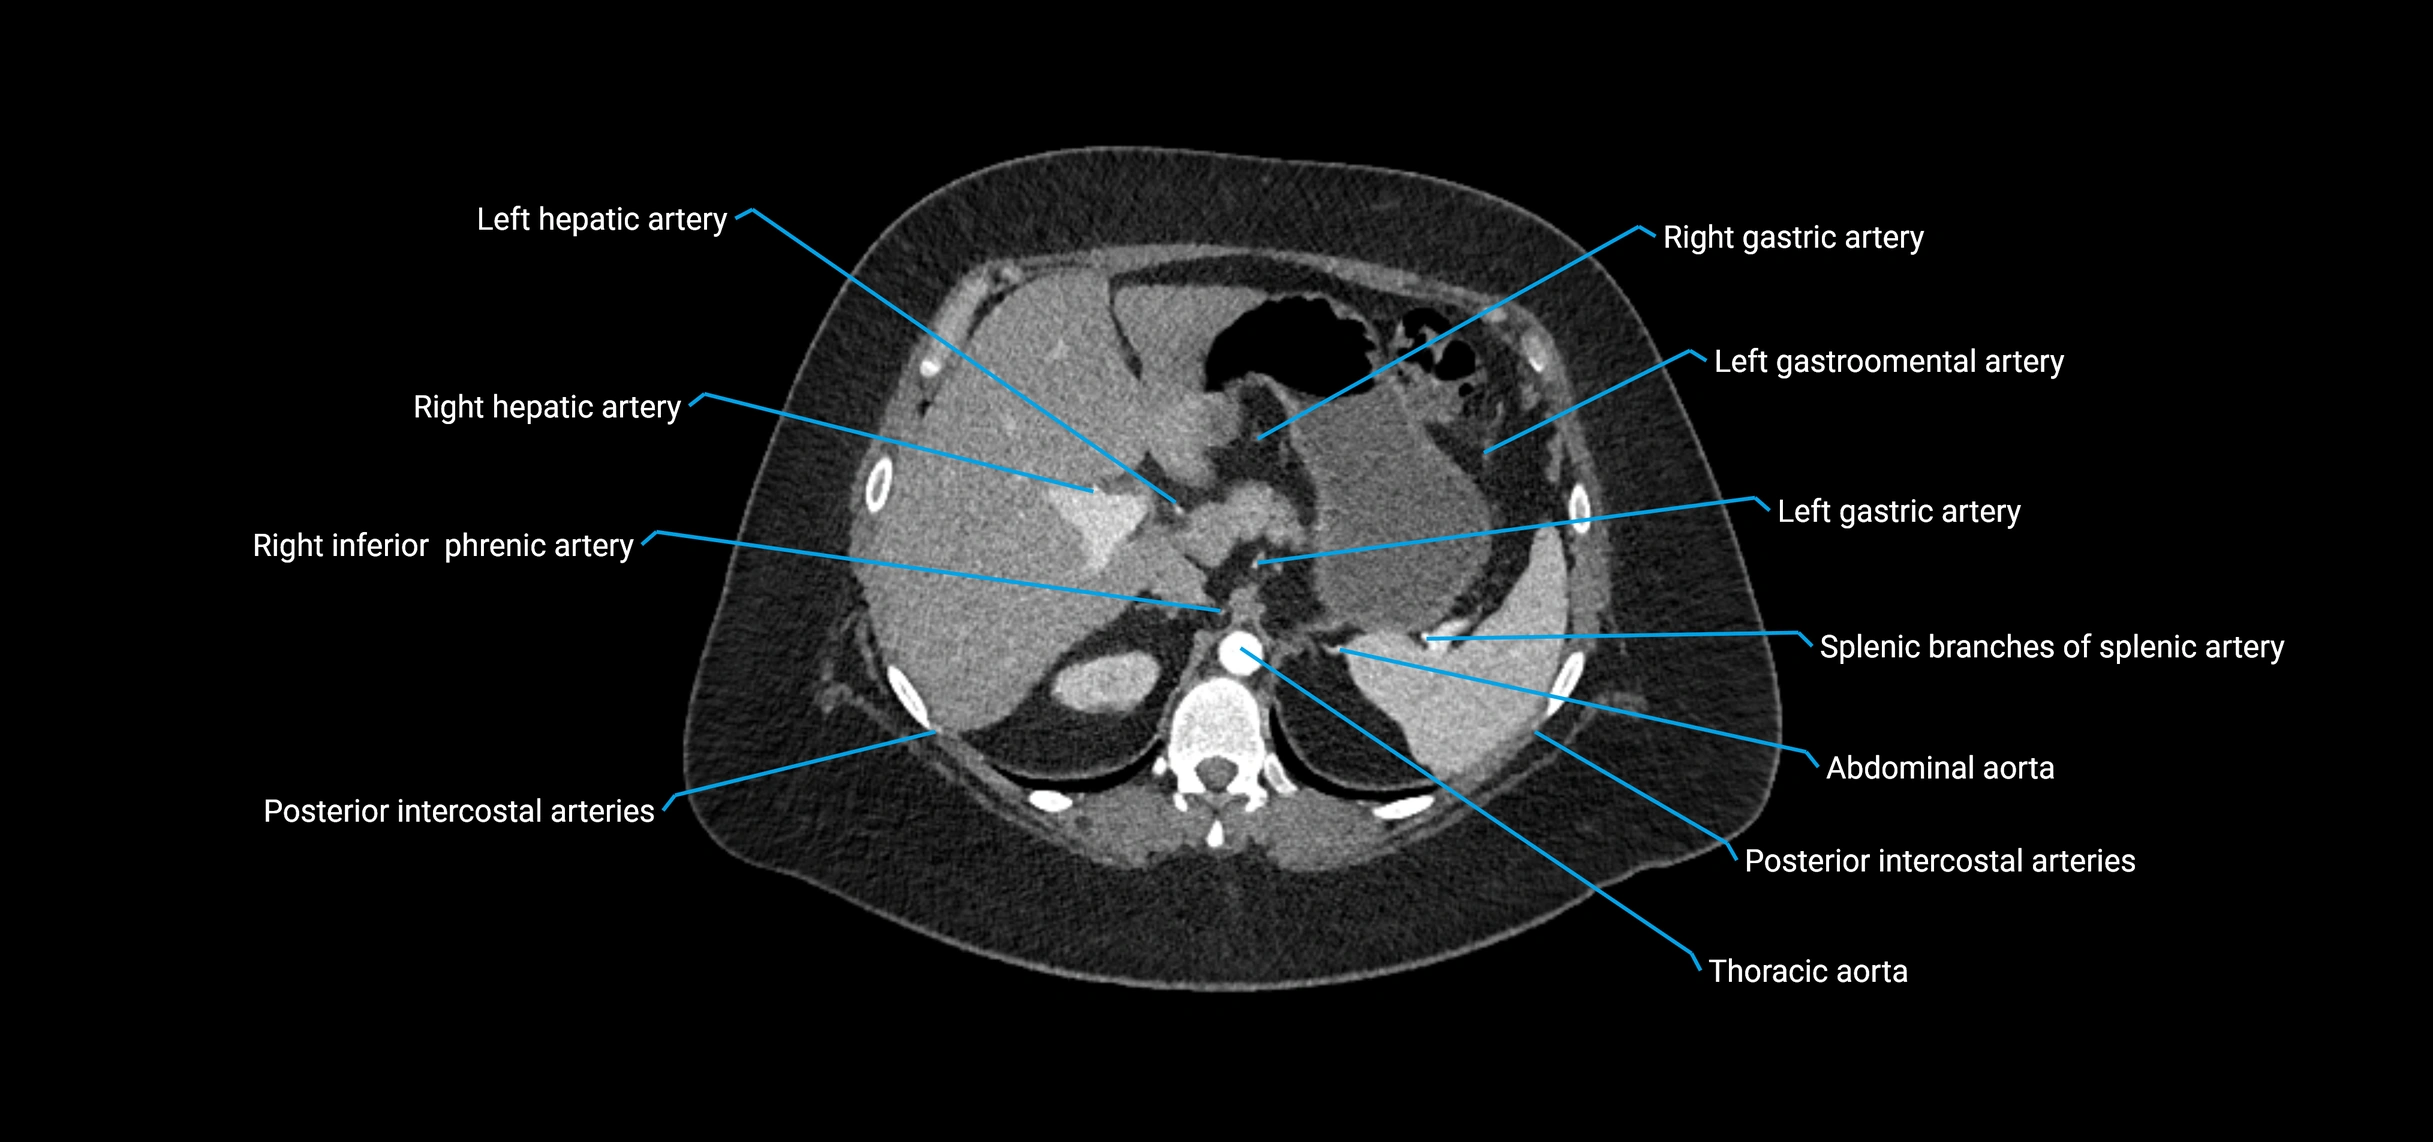

CT Appearance

Non-contrast CT:

• Appears as a tubular soft tissue structure anterior to vertebral bodies

• Calcified atherosclerotic plaques appear as hyperdense foci along the wall

• Useful for screening abdominal aortic aneurysm (AAA) size and mural calcification

Contrast-enhanced CT (CTA):

• Gold standard for abdominal aortic imaging

• Provides excellent detail of lumen, wall, aneurysm, thrombus, and branch vessels

• Multiplanar and 3D reconstructions help in aneurysm measurement, stent graft planning, and dissection evaluation

• Detects acute rupture, traumatic injury, or occlusion with high sensitivity